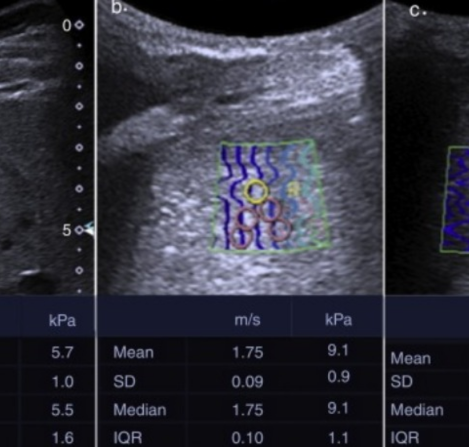

Elastografía

Las elastografía utiliza vibraciones de baja frecuencia durante un ultrasonido o una RMN para medir la rigidez (o elasticidad) de órganos internos. Es particularmente útil para detectar la presencia y la gravedad de enfermedades del hígado. Con un procedimiento de...